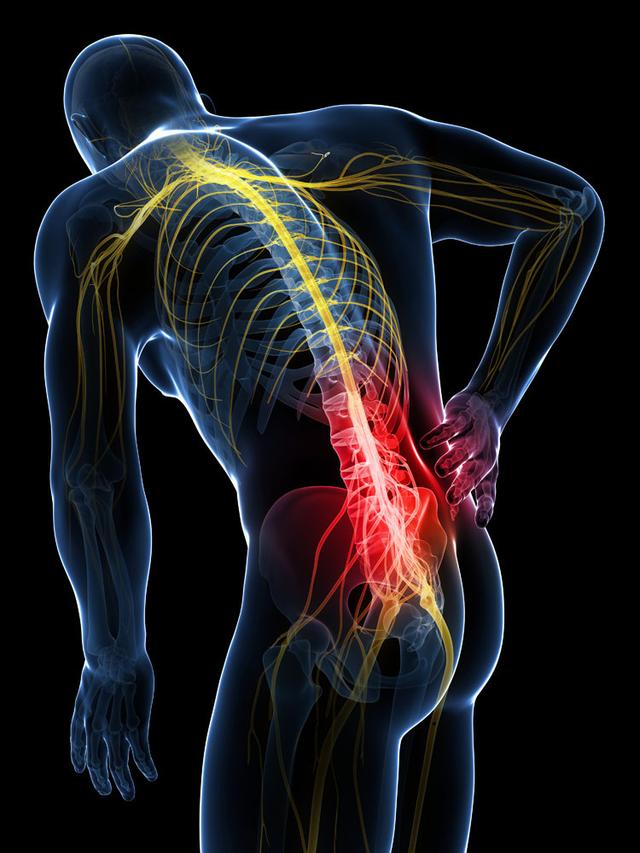

从一方面来说,人类是弱小的,容易生病,容易受伤,但从另一方面来说,人类也是强大的...